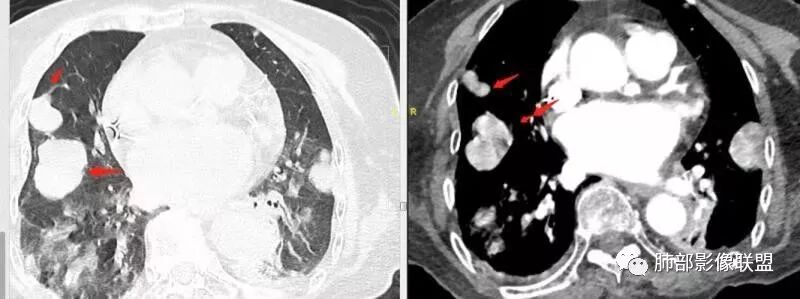

老年女性,两肺多发球形结节,边缘光滑,部分位于胸膜下,纵隔淋巴结肿大不明显,胸水少量,增强后强化明显,考虑转移,肉瘤转移的可能,补充下病史。气管内新生物,是不是二元,息肉或肿瘤

老年女性,间断咯血两年。影像:气管内带蒂结节,边缘光滑明显强化。左肺下叶背段支气管截断,远端不张。两肺散在大小不等结节及磨玻璃影,明显强化,磨玻璃影考虑合并出血可能。纵隔多发淋巴结肿大,两侧支气管受压。综合考虑:肺癌伴两肺转移。原发气管结节还是左肺下叶背段?腺样囊性癌?类癌?

气管占位与肺内肿块血供异常丰富,接近大动脉强化,可以考虑同源

而血供丰富的转移瘤不多,常见于甲状腺癌,肾透明细胞癌,肉瘤及少数腺癌。没给平扫,不知道有没有钙化,钙化常见于甲状腺癌及成骨类的肉瘤。